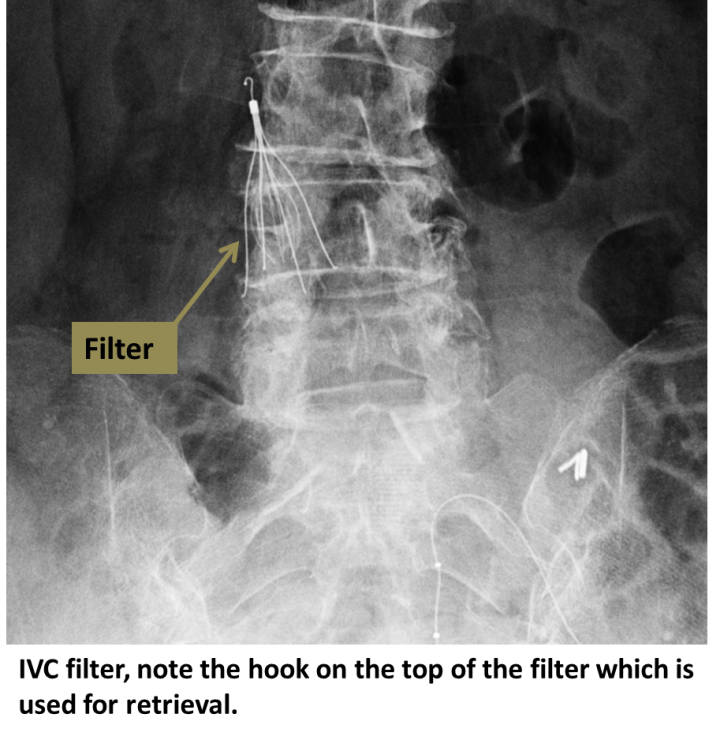

[Figure, IVC filter xray Image courtesy S Bhimji MD] StatPearls NCBI Bookshelf Ivc Filter X Ray Inferior vena cava filters (ivc filters) are indicated as a treatment to prevent pulmonary embolism in a select group of patients that have venous thromboembolism. Inferior vena cava filters are devices used to prevent blood clots from traveling to the lungs. A dye (contrast agent), which usually contains iodine, is injected directly into the. During inferior vena cava (ivc) filter. Ivc Filter X Ray.